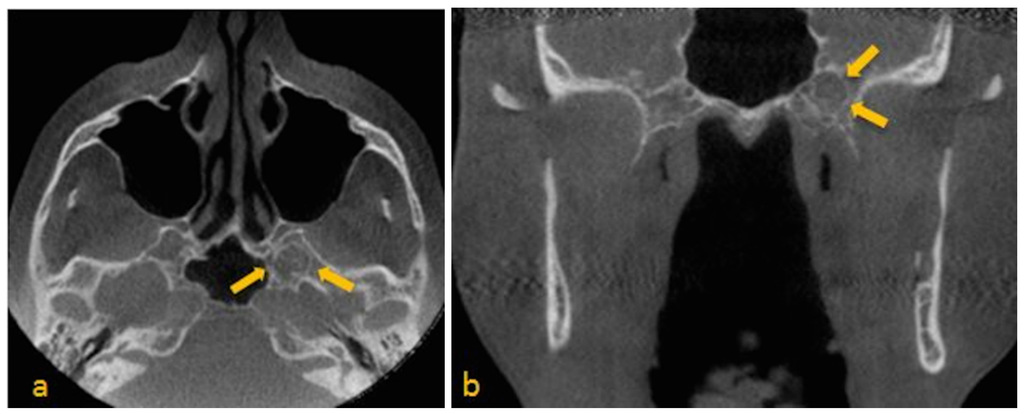

- Lesion must be non-expansile with sclerotic, well-defined margin, and should be located at a site of normal pneumatization. Evidence of fatty content should be present. Internal curvilinear calcifications should be noted on CT images [1].

- Since, sphenoid sinus is closely related to several vital neurovascular structures such as internal carotid artery and optic nerve, any associated skull-base foramina should remain intact and patent.